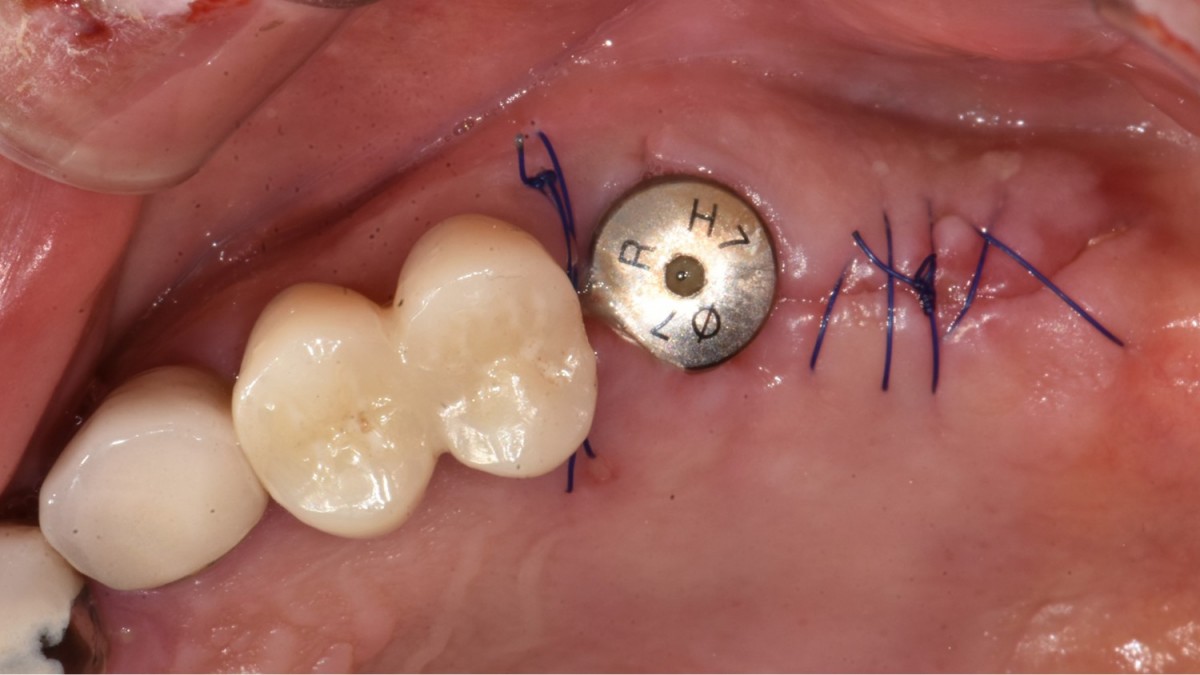

▲2 implants were placed. ArumDentistry NB1 5*10 (30Ncm) in the 1st molar and 5*10 (10Ncm) in the 2nd molar.

▲HA was inserted into the membrane with a hole in the middle and then inserted into the place where the Direction Pin was pulled out